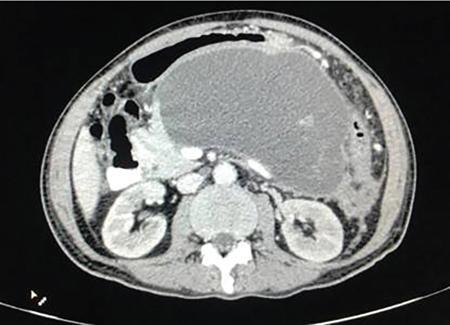

The image showcases two classical signs in GI radiology which are the ‘widening of C loop of duodenum’ and the ‘antral pad sign’. Both the signs are typically described in masses of head of pancreas. A comment on the mucosal lining (regular/irregular) may give a pointer towards the mass being malignant. However, this is a nonspecific sign giving indication of a mass effect and has a variety of differentials. The final diagnosis is reached with the help of cross-sectional imaging and/or endoscopy/biopsy. CECT abdomen in this case confirmed it to be a case of carcinoma pancreas (Fig. 7.4.6.1).

Image

Fig. 7.4.6.1 CECT showing a mass in the head of pancreas.

Carcinoma head of pancreas

• a) Widening of C loop with irregular mucosal margins.

• b) Antral pad sign.

• c) Frostberg inverted 3 sign.

• d) Definitive diagnosis with CECT.